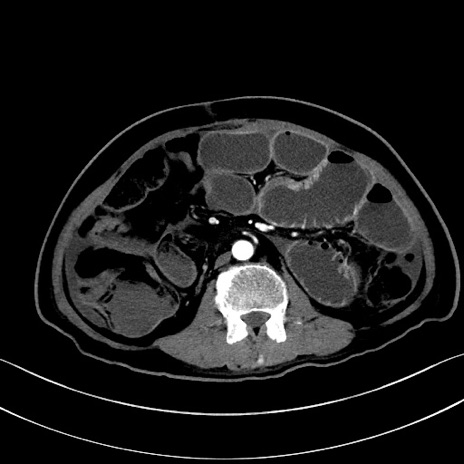

症例28(横断像)

【症例】60歳代男性

【主訴】嘔吐

【現病歴】胃癌にて胃全摘後。食思不振が悪化し、夜中に嘔吐することがある。

【既往歴】胃癌、胃全摘、脾摘、胆摘後

【データ】WBC 5900、CRP 10.56